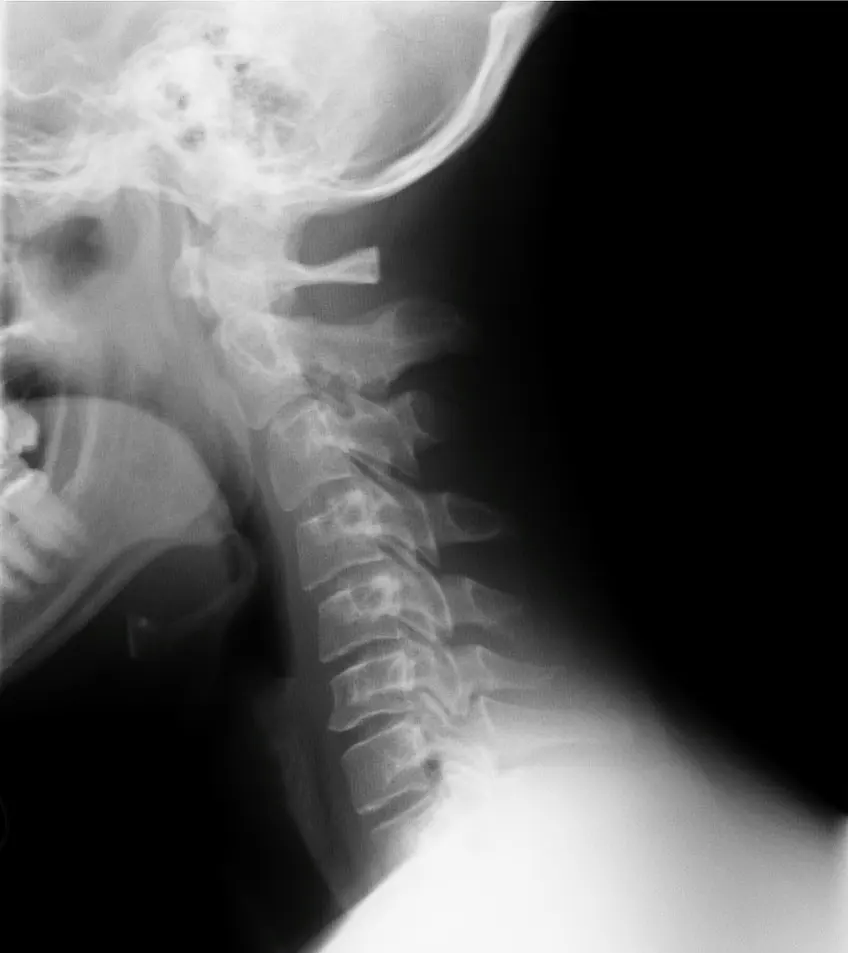

Las vértebras cervicales son siete en total y constituyen la estructura ósea del cuello. La vértebra más superior, el atlas, sostiene la cabeza y garantiza su adecuada rotación junto con la segunda cervical, el eje. Estas dos vértebras tienen una estructura muy específica y son claves para la rotación de la cabeza.

Las cervicales inferiores (de C3 a C7) acentúan esta movilidad y garantizan la estabilidad de la cabeza. Están en constante interacción con el entorno a través de la vista, el olfato y el gusto. Están articuladas entre sí mediante discos intervertebrales, estructuras fibrocartilaginosas que aseguran los movimientos y la elasticidad del cuello.